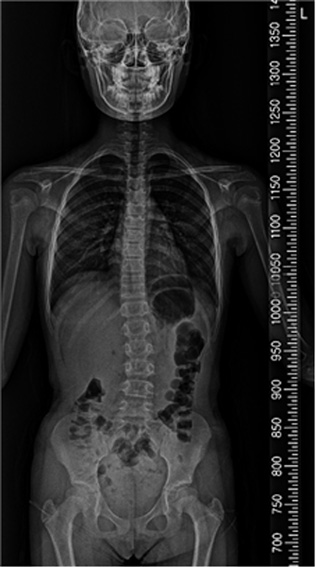

척추 측만증은 80%가 사춘기 때 발생하며, 사춘기 여아의 10~14%, 사춘기 남아의 5%에서 나타나는 것으로 알려져 있습니다. 성조숙증이 있는 아이들은 더 어린 나이에 급성장이 온 것이기 때문에 척추 측만증이 생길 가능성이 더 높습니다. 성장호르몬 치료를 하는 경우에도 사춘기때처럼 급성장을 하기 때문에 척추 측만증이 생길 가능성이 더 높습니다. 물론 이는 약물 부장용이 아닌, 일종의 성장 부작용인 셈입니다. 척추 측만증은 심할수록, 골연령이 어릴수록, 그리고 역연령이 어릴수록 점점 더 심해질 가능성이 높으며, 따라서 가능하면 조기에 발견하여 치료하는 것이 좋습니다. (from Lonstein & Carlson) 이렇게 척추 측만증은 일종의 성장기 합병증으로 볼 수 있으며, 따라서 성장판이 닫칠 때까지 더 진행될 확률이 높고 대신 성장판이 닫치면 진행도 멈추게 됩니다.

척추 측만증 : 앉아 있기가 힘이 들며 어깨 높이가 다른등 척추 부위 통증 및 걸음걸이, 자세등에 다양한 불편감 호소.